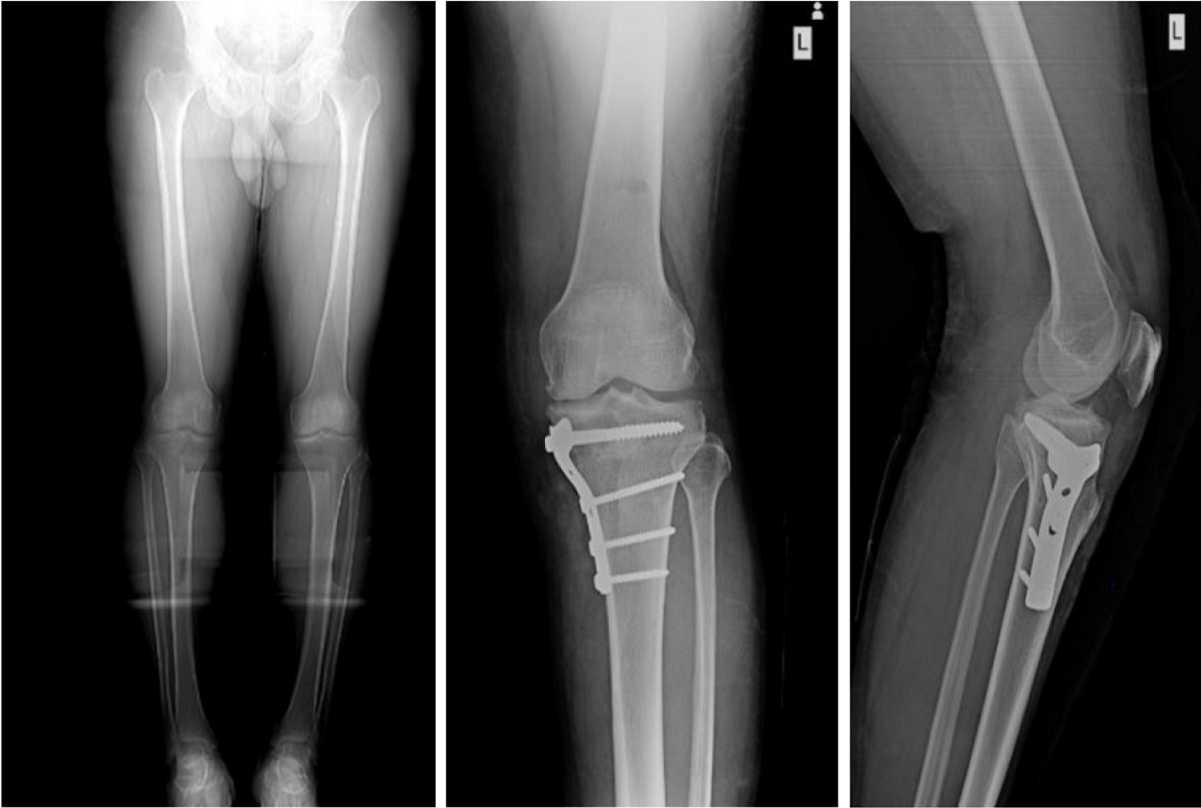

عمل استئوتومی چیست و چه کابردی دارد؟

جراحی پای پرانتزی و مراقبت های بعد از آن